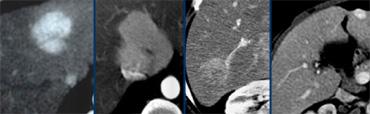

Ung thư biểu mô tế bào gan kích thước nhỏ trên nền gan xơ: không quan sát thấy trên CT không tiêm thuốc (trái), hiện rõ trong thì động mạch (giữa) và không quan sát thấy trong thì tĩnh mạch cửa (phải)

Khả năng phát hiện một tổn thương gan phụ thuộc vào sự chênh lệch tỷ trọng giữa tổn thương và nhu mô gan bình thường.

Trên CT không tiêm thuốc cản quang (NECT), các khối u gan thường không quan sát được do độ tương phản vốn có giữa mô u và nhu mô gan xung quanh quá thấp.

Chỉ một số ít khối u có chứa vôi hóa, thành phần nang, mỡ hoặc xuất huyết mới có thể được phát hiện trên NECT.

Do đó, cần tiêm thuốc cản quang tĩnh mạch để tăng khả năng hiển thị của các tổn thương.

Khi tiêm thuốc cản quang tĩnh mạch, cần hiểu rằng gan có nguồn cung cấp máu kép.

Nhu mô gan bình thường được cung cấp máu 80% từ tĩnh mạch cửa và chỉ 20% từ động mạch gan, do đó sẽ ngấm thuốc trong thì tĩnh mạch cửa.

Tuy nhiên, tất cả các khối u gan đều nhận 100% nguồn cung cấp máu từ động mạch gan, vì vậy khi ngấm thuốc sẽ xảy ra trong thì động mạch.

Sự khác biệt về nguồn cung cấp máu này dẫn đến các kiểu ngấm thuốc khác nhau giữa khối u gan và nhu mô gan bình thường trong các thì tiêm thuốc cản quang khác nhau (hình).

Khả năng phát hiện tổn thương phụ thuộc vào sự chênh lệch tỷ trọng giữa gan và tổn thương. TRÁI: Thì động mạch cho thấy tăng sản nốt khu trú (FNH) tăng mạch. GIỮA: Thì tĩnh mạch cửa cho thấy di căn giảm mạch. PHẢI: Thì cân bằng cho thấy ung thư biểu mô đường mật tương đối tăng tỷ trọng

Trong thì động mạch, các khối u tăng mạch sẽ ngấm thuốc qua động mạch gan khi nhu mô gan bình thường chưa ngấm thuốc, do thuốc cản quang chưa vào hệ thống tĩnh mạch cửa.

Các khối u tăng mạch này sẽ hiện ra là các tổn thương tăng tỷ trọng trên nền gan tương đối giảm tỷ trọng.

Tuy nhiên, khi nhu mô gan xung quanh bắt đầu ngấm thuốc trong thì tĩnh mạch cửa, các tổn thương tăng mạch này có thể bị che khuất.

Trong thì tĩnh mạch cửa, các khối u giảm mạch được phát hiện khi nhu mô gan bình thường ngấm thuốc tối đa.

Các khối u giảm mạch này sẽ hiện ra là các tổn thương giảm tỷ trọng trên nền gan tương đối tăng tỷ trọng.

Trong thì cân bằng, vào khoảng 10 phút sau khi tiêm thuốc, các khối u trở nên hiện rõ khi chúng thải thuốc chậm hơn hoặc nhanh hơn so với nhu mô gan bình thường.

Các tổn thương này sẽ trở nên tương đối tăng tỷ trọng hoặc giảm tỷ trọng so với gan bình thường.